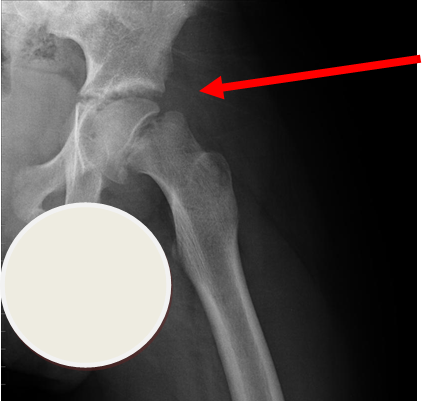

4. Slipped Upper Femoral Epiphysis (SUFE)

Subtle left sided SUFE.

Case courtesy of Dr Gagandeep Singh, Radiopaedia.org. From the case rID: 7688

Usually occurs in late childhood / adolescence and is more common in boys than girls (2:1).  It also presents more commonly in children whose weight is above the 90th centile.  Bilateral in 25% of cases.  Onset can be acute or subacute (ie children may present with >1day h/o pain or limp).  Children may walk with an antalgic gait out-toeing, with shortening of the affected limb.  If the slip is acute, the child may be unable to walk.  Diagnosis is made radiologically and frog-lateral views are required as it may be missed on AP views.  Urgent orthopaedic opinion is required.  Unstable slips can lead to avascular necrosis of the femoral head.

Investigation

• X-ray - AP pelvis with frog lateral view (must be discussed with ortho 1st on call / ED consultant if child <8 years old)